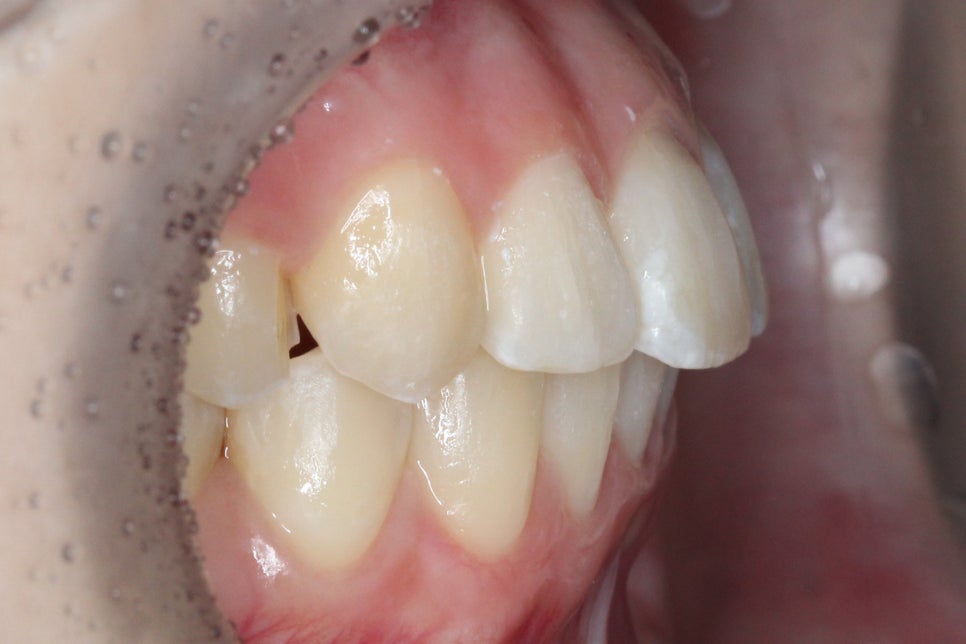

송곳니덧니 교정 전 교합평면을 보면

송곳니의 높이가 다른 치아들보다

월등히 높은 곳에 위치한 것을 확인할 수 있는데요,

반대쪽 치열과 비교해보면 확연하게

그 차이를 알 수 있습니다.

송곳니덧니 교정 후 교합평면을 보면

높은 위치에 있던 송곳니가

솟아난 부분 없이 가지런하게

교정된 모습으로, 반대쪽 치열과

비교했을 때 일정한 높이로

배열된 것을 확인할 수 있습니다.